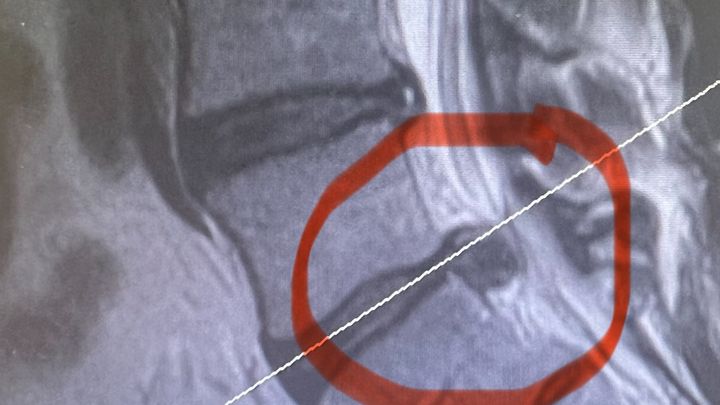

About a month ago I hurt my back. I have only missed one day of work and that was the day I went to the emergency room. I have 2 herniated discs one at L5 and one at S1. I have finally received a date for the surgery on January 25. This will be a full discectomy of my S1. Please pray before you give. I would rather pay you back the money then just ask you to donate so if that works please let me know. I also know this is the worst time to have money troubles. Thank you so much. I love all the well wishes and messages that everyone has sent me on Facebook.